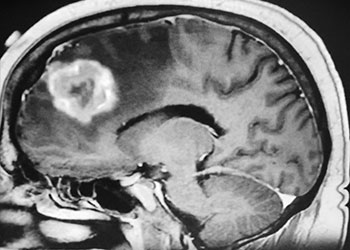

Brain:

Atypical Convexity Meningioma

Author: Jonathan L. Brisman M.D., F.A.C.S., Read More!

Grade II Oligodendroglioma

Author: Ramin Rak M.D., F.A.A.N.S., F.C.N.S., Read More!

Brain Metastasis

Author: Michael Brisman M.D., F.A.C.S., Read More!